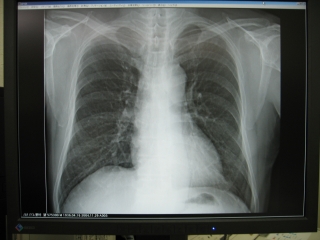

縮小率100%でアナログX線画像と同じサイズであり、モニター画面であるが、アナ

ログX線フィルム画像よりも美しく鮮明である。

写真4.制御装置のモニターにX線画像が表示

写真5.LF−C1のモニターに等倍表示

X線撮影後、約2分で診察室に置いたモニターに撮影したX線画像が表示されます。これを等倍表示にしておくと、モニターには通常のアナログX線フィルムと同じ大きさで表示されます。EIZO 21.3インチの液晶モニターに表示された画像は、アナログX線フィルよりも鮮明で、これだけ鮮明なら臨床的にはフィルムに勝るとも劣らないと思います。その画像が従来のフィルム現像よりもかなり早く表示されるのだから非常に有用です。(写真5参照)